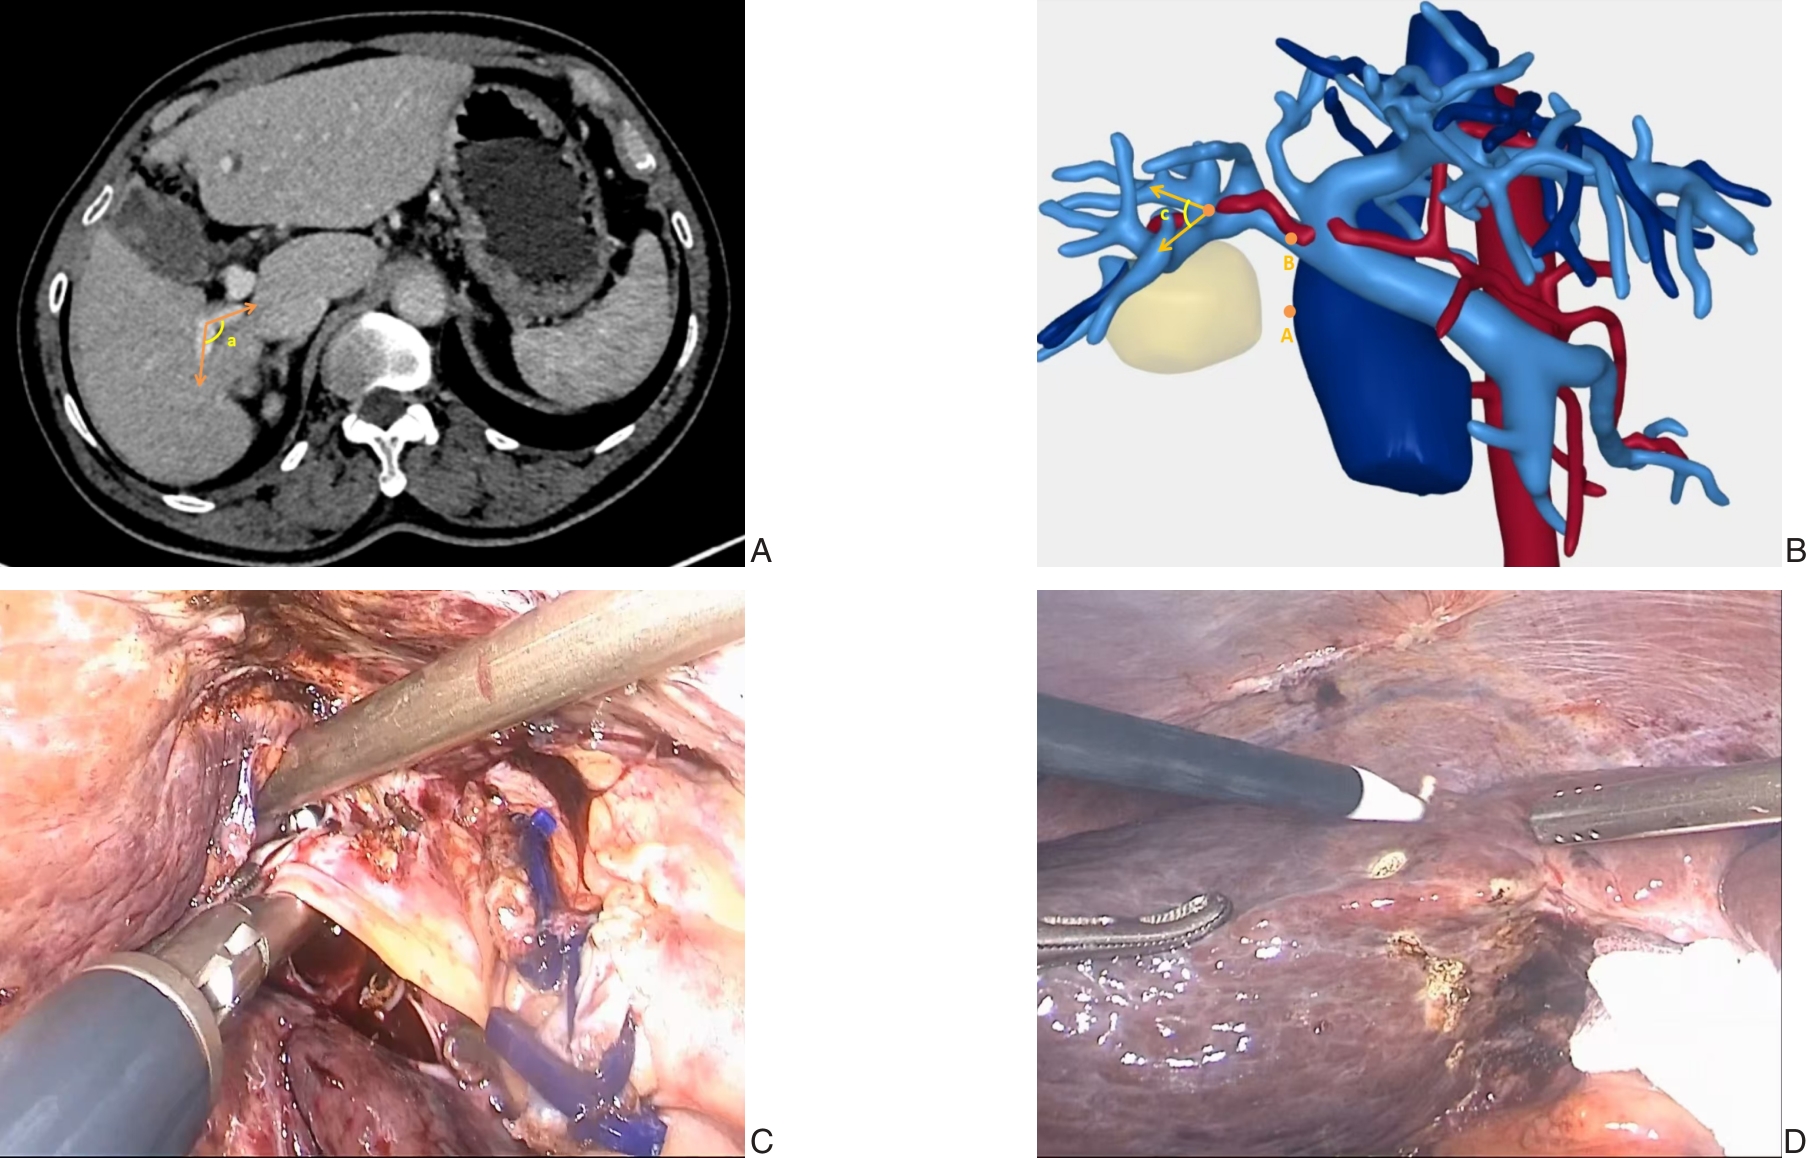

• Application of augmented reality navigation combined with indocyanine green fluorescence imaging in laparoscopic resection of central hepatic tumors

2026, 35(1):88-96. DOI: 10.7659/j.issn.1005-6947.250468

Abstract (100) HTML (82) PDF 2.06 M (167) Comment (0) Favorites

Abstract:Background and Aims Laparoscopic resection of centrally located hepatic tumors remains technically demanding due to the complex anatomical relationships with major vascular structures. Conventional intraoperative ultrasound or indocyanine green fluorescence imaging (ICG-FI) alone has limitations, particularly in visualizing deep anatomical structures. This study aimed to evaluate the clinical value of augmented reality (AR) navigation combined with ICG-FI in laparoscopic resection of central hepatic tumors.Methods A retrospective analysis was conducted on 38 consecutive patients who underwent laparoscopic resection of central hepatic tumors guided by AR navigation combined with ICG-FI between May 2022 and March 2025. Intraoperative navigation performance, surgical parameters, and perioperative outcomes were assessed.Results All 38 procedures were completed laparoscopically without conversion. The intraoperative tumor fluorescence detection rate was 100%. The mean operative time was (324.9 ± 132.4) min, and the median intraoperative blood loss was 400 (50-1 200) mL. The mean registration error was (6.3±0.6) mm. The median number of predicted and verified vessels was 6 (4-8) and 7 (5-10), respectively. R0 resection was achieved in all patients, with a mean surgical margin of (1.5±0.5) cm. The postoperative complication rate was 13.2%, with no severe complications such as intra-abdominal hemorrhage, gas embolism, or liver failure. The median postoperative hospital stay was 9 (4-20) days. During a median follow-up of 20 months, no tumor recurrence was observed.Conclusion The combined use of AR navigation and ICG-FI enables intraoperative prediction and verification of critical vascular structures and facilitates precise control of the transection plane in laparoscopic resection of central hepatic tumors. This technique improves surgical precision and safety and shows promising clinical potential.